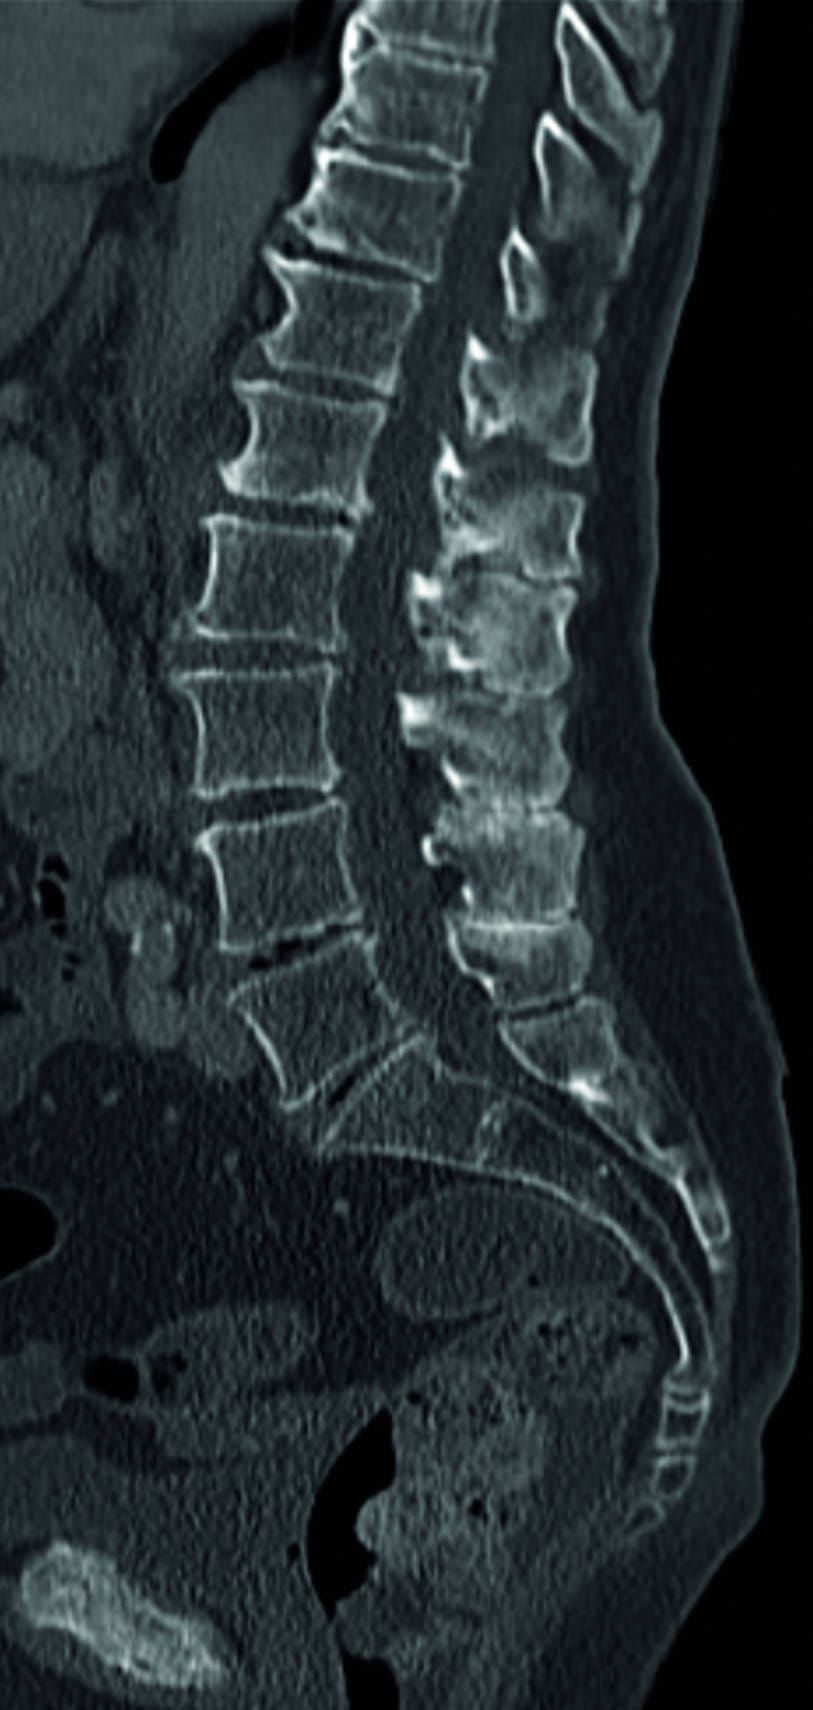

The cultured OECs were then transplanted into the spinal cord stumps above and below the injury in 100 micro injections, and the 8 mm gap created by the knife wound was bridged by 4 strips of nerve from Mr Fidyka’s leg. The transplanted nerve acted as a scaffold and the OECs allowed the nerve axons in the spine to regrow. As all the cells came from the patient’s body, there was no risk of rejection.

Imaging has shown that the grafts had bridged the left side of the spinal cord, where the majority of the nerve grafts were implanted.